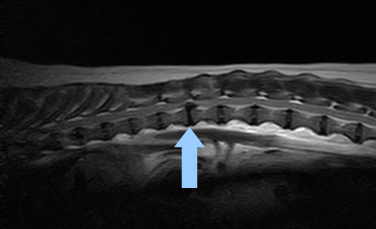

症例② 胸腰部椎間板ヘルニア

元気・食欲がない、動きが鈍いため来院

| レントゲン検査 | 胸腰椎部椎間狭窄 |

| 胸腰部MRI検査 | 中等度の椎間板逸脱がみとめられた |

| 診断・治療 | 胸腰椎椎間板ヘルニア(グレードⅡ)の疑いで、安静とステロイドの投与をおこなったが、進行したため、外科的治療 |

![]() 胸腰部MRI検査 矢印が飛び出した椎間板 下から上の脊髄神経を圧迫している |